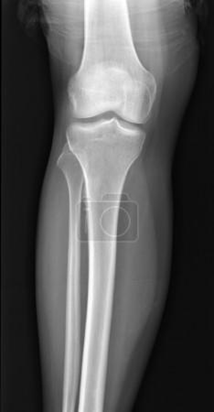

РОЗПІЗНАЙТЕ НА РЕНТГЕНОГРАМІ СУГЛОБ, ЩО СКЛАДАЄТЬСЯ З ТРЬОХ СУГЛОБІВ, ЯКІ МАЮТЬ СПІЛЬНУ КАПСУЛУ.

варіанти відповідей

Запитання 51

РОЗПІЗНАЙТЕ СУГЛОБ, ЯКИЙ ЗАБЕЗПЕЧУЄ РУХИ ГОМІЛКИ.

СУГЛОБ СКЛАДНИЙ. УТВОРЕНИЙ СУГЛОБОВИМИ ПОВЕРХНЯМИ МЕДІАЛЬНОГО І ЛАТЕРАЛЬНОГО ВИРОСТКІВ, ЯКІ Є В ОБОХ КІСТКАХ, ЩО ЙОГО УТВОРЮЮТЬ. РОЗПІЗНАЙТЕ СУГЛОБ.

КОЛІННИЙ С.

ЛІКТЬОВИЙ С.

ГОМІЛКОВО--СТОПНИЙ С.

ПРОМЕНЕВО-ЗАП'ЯСТКОВИЙ С.